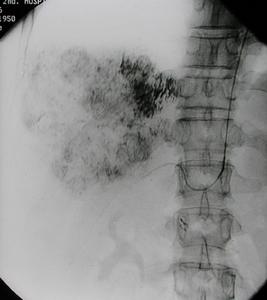

3、血管造影或數字減影血管造影(圖1)它可以提供最為詳盡準確的病情資料,例如病變部位、範圍程度為血管成形手術或手術方式的選擇提供依據。